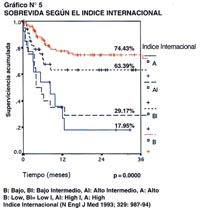

En el Gráfico N° 5, se muestra la supervivencia acumulada a 36 meses de acuerdo al índice Internacional y claramente se puede objetivar la diferencia entre los distintos grupos previamente establecidos, esto es, los pacientes con índice internacional bajo tienen una supervivencia a 3 años del 74.43%, los pacientes con índice internacional bajo intermedio tienen una supervivencia de 63.39%, los pacientes con índice internacional alto intermedio tienen una supervivencia de 29.17%, y finalmente los pacientes con índice internacional alto alcanzan una supervivencia de sólo 17.95%. De acuerdo a estos resultados, nosotros podemos decir que confirmamos para el caso de nuestros pacientes la validez de dicho índice Internacional, el cual presenta una significancia estadística de p=0.0000 y log rank de 30.59.